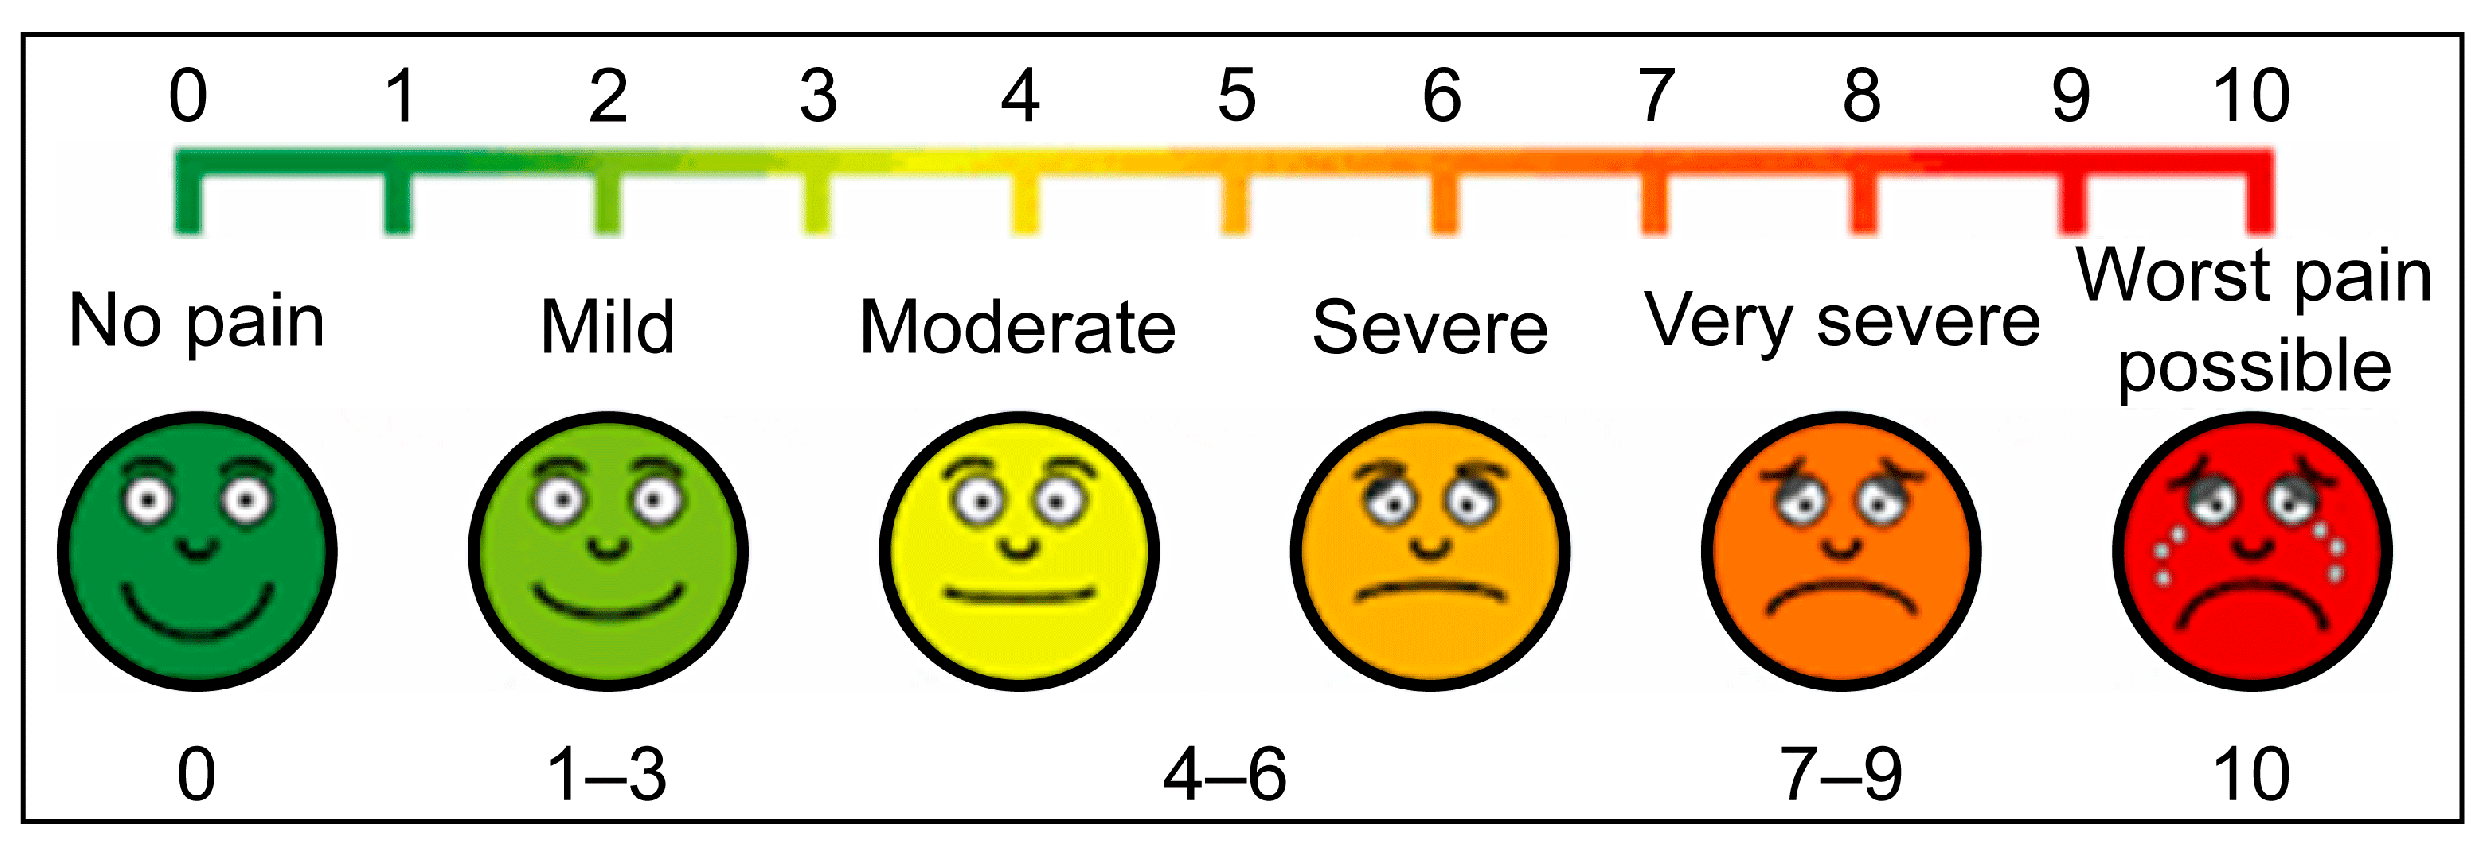

| VAS Score, median (Q1–Q3) | 4.0 (2.5–7.5) | 1.0 (0–2.0) | <0.001 * |